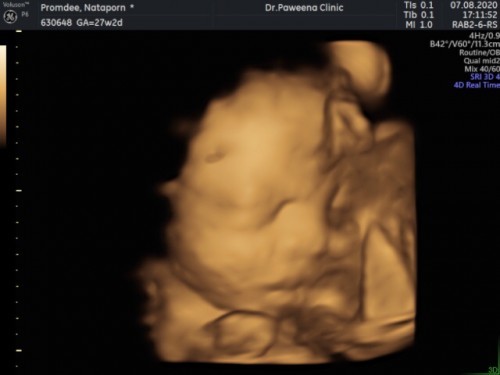

มาโชว์ภาพอัลตราซาวด์ของเจ้าตัวน้อยกันค่ะ

บ้านนี้ 27 week 2 day